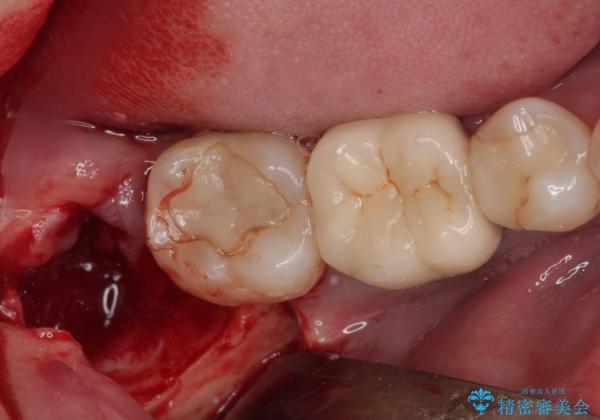

しっかり麻酔が効いたことを確認してから安全に抜歯を行いました。